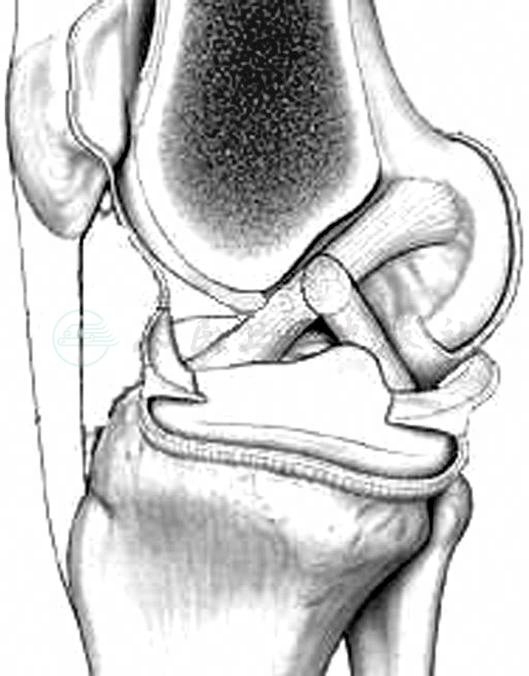

前交叉韧带位于膝关节的中央,起自股骨外髁内侧面后部,向前、内方向走形,止于两侧胫骨髁间棘的前内区域。股骨附丽区呈椭圆形或半圆形(图1A),附丽区长轴与股骨纵轴交角是26°。胫骨附丽区呈三角形(图1B),内侧为胫骨平台内侧关节面,外侧为外侧半月板前角,前方为半月板横韧带。

图1前交叉韧带附丽区

A.股骨附丽区;B.胫骨附丽区